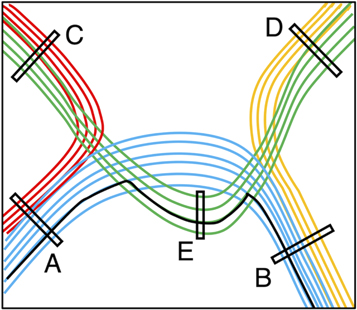

Targeted tractography utilises strategically placed ROIs typically based on a priori knowledge about the WM tract anatomy, to impose anatomical constraints for streamline propagation/tracking (see figure 8). They include: the seed ROI, which defines the starting point of streamline tracking; the inclusion ROI (also known as the 'AND' ROI or 'waypoints'), which defines the obligatory tract passage where the tract is known to pass through; and the exclusion ROI (also known as the 'NOT' ROI), which defines the region the tract is known not to pass through. Streamlines intersecting the exclusion ROI are rejected.

Figure 8. A schematic illustration demonstrating the regions-of-interest (ROIs) strategy used for targeted tractography. Here, we have four different coloured white matter tracts organised in complex fibre arrangements, including crossing, kissing, and overlapping patterns. To reconstruct the blue-coloured white matter tract, the tracking ROIs are placed based on a priori anatomical knowledge about all four white matter tracts. ROI-A and ROI-B can be used as either the seed ROI (representing the tracking starting point) or the inclusion ROI (representing the obligatory passage of this tract). ROI-C, ROI-D, and ROI-E are used as exclusion ROIs (representing regions where the blue-coloured tract is known not to pass). Note that without using the ROI-E as an exclusion ROI, false positive reconstruction can be produced (i.e. the solid black-coloured streamline) due to streamlines propagating over the crossing-fibre region between the blue- and green-coloured white matter tracts.